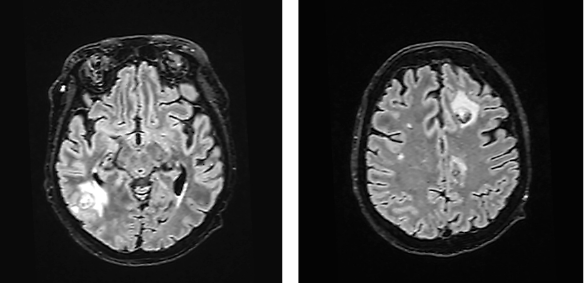

The patient’s condition deteriorated during transportation, requiring re-intubation. Neurosurgical intervention was not considered viable. Consequently, the antibiotic regimen was expanded to include Ceftriaxone, Vancomycin, Metronidazole, and Sulfamethoxazole-Trimethoprim, targeting a broader spectrum of pathogens potentially responsible for brain abscesses. Despite plans to conduct diagnostic tests for HIV, syphilis, toxoplasmosis, and Listeria from the abscess aspirates, the patient’s condition rapidly deteriorated, becoming critically unstable. This acute decline was marked by severe respiratory insufficiency and profound bradycardia, necessitating immediate cardiopulmonary resuscitation (CPR) and the urgent administration of Atropine. Finally, due to prolonged intubation, it was decided to form a tracheostomy. Subsequent MRI showed a reduction in the abscess size (Fig. 3), and the patient was transferred to the Neurology Department for continued care.